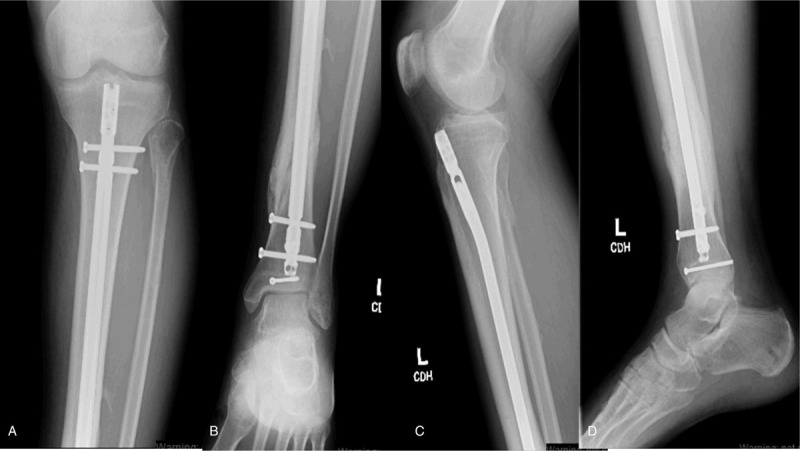

Figure 2.

(A–D) Anteroposterior (A, B) and lateral (C, D) radiographs of the tibia showing a distal third oblique tibial shaft fracture. There are concomitant proximal fibula and posterior malleolar fractures as well.

(A–D) Anteroposterior (A, B) and lateral (C, D) radiographs of the left tibia 6 months postoperatively following intramedullary nailing of diaphyseal tibia fracture, percutaneous screw fixation of posterior malleolar fracture, and closed management of proximal fibula fracture. Interval callus is observed about all 4 cortices consistent with fracture union.